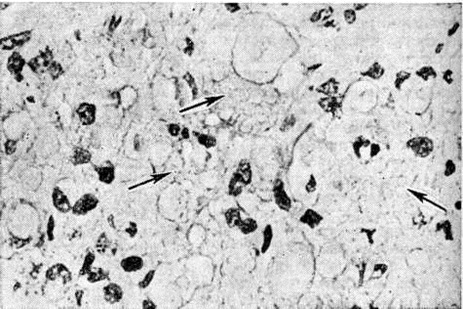

Рис. 3.

Микроскопическая картина кожного инфильтрата при лепроматозном типе лепры: стрелками указаны скопления липидов в цитоплазме лепрозных клеток. Окраска Суданом III; × 500.

Рис. 1—6.

Микроскопические картины поражений при различных формах лепры.